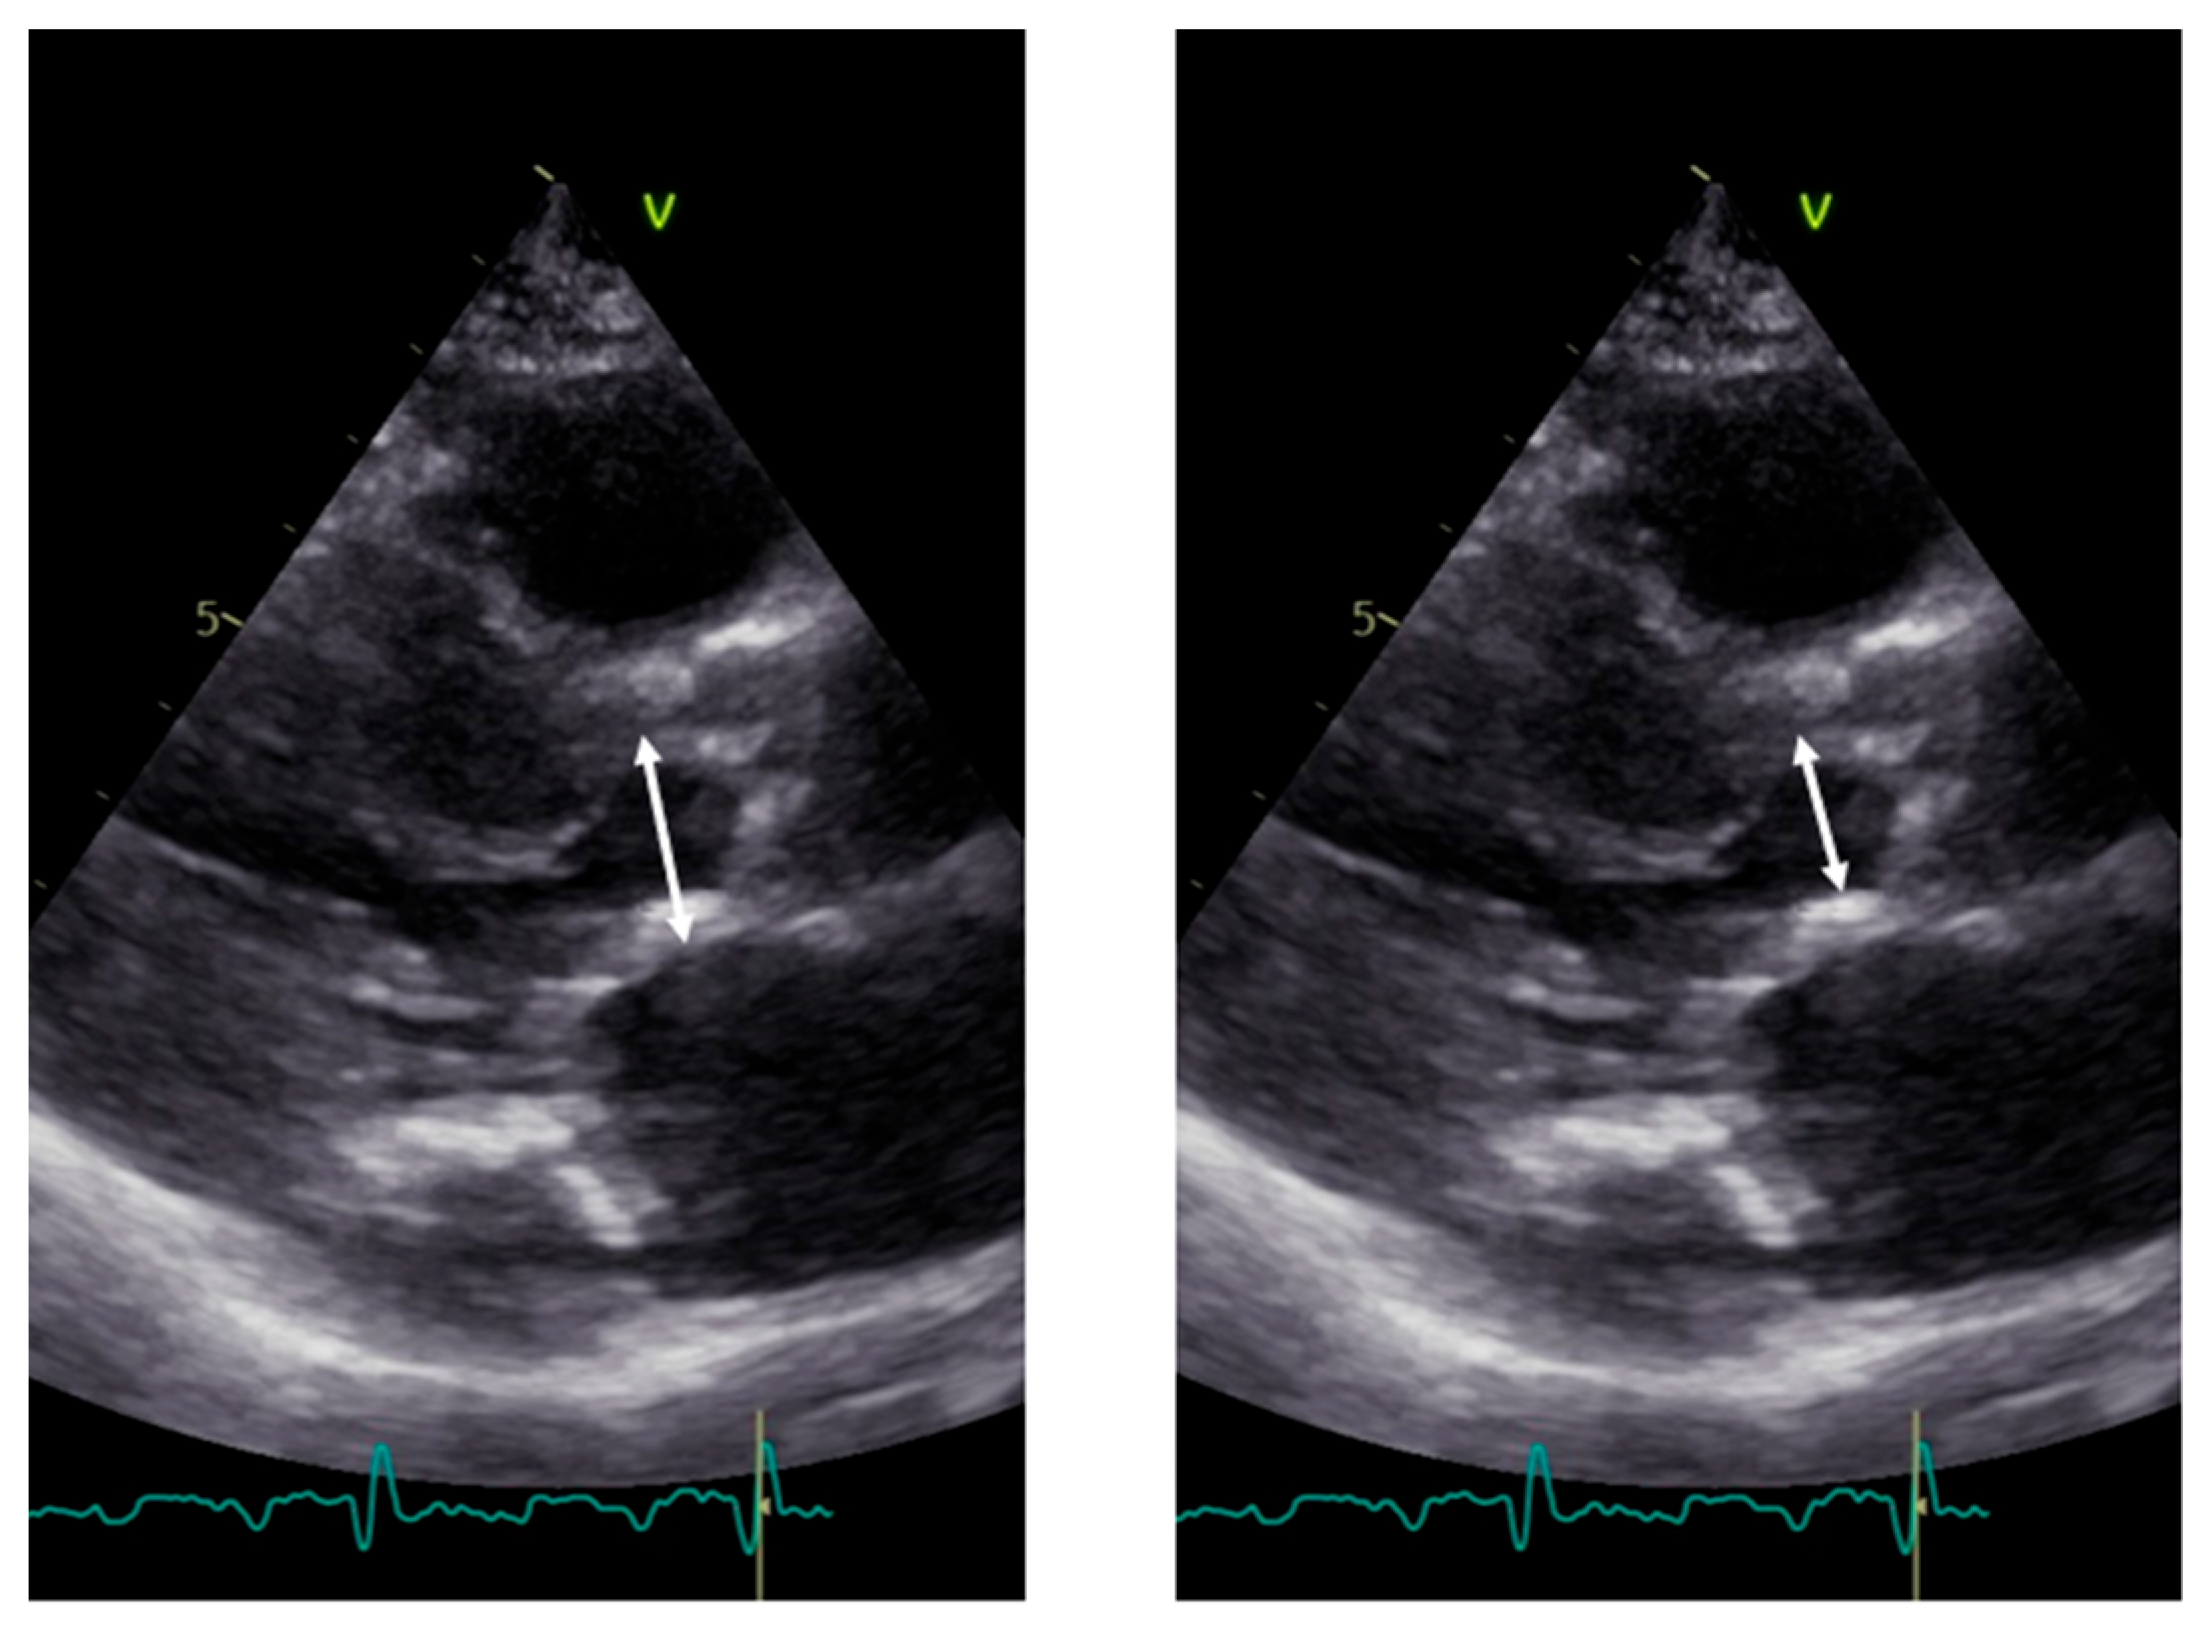

Aortic morphology and movement. From the long axis, aortic valve morphology and movement could be assessed; however, in general, a short axis is additionally required. When stenosis is present, 2D images show a marked increase in echogenicity consistent with calcification of the leaflets. A systolic leaflet separation of at least 15 mm by 2D or 2D-guided M-Mode reliably excludes severe stenosis [23]. If less than 15 mm, the degree of stenosis can range from mild to severe (Figure 5.).

Figure 5. Example of M-Mode tracing of the aortic valve. Note the reduced opening, inferior to 15 mm, suggestive of aortic stenosis although not of a specific degree. The box indicates the aortic valve opening, the arrow the maximal opening.